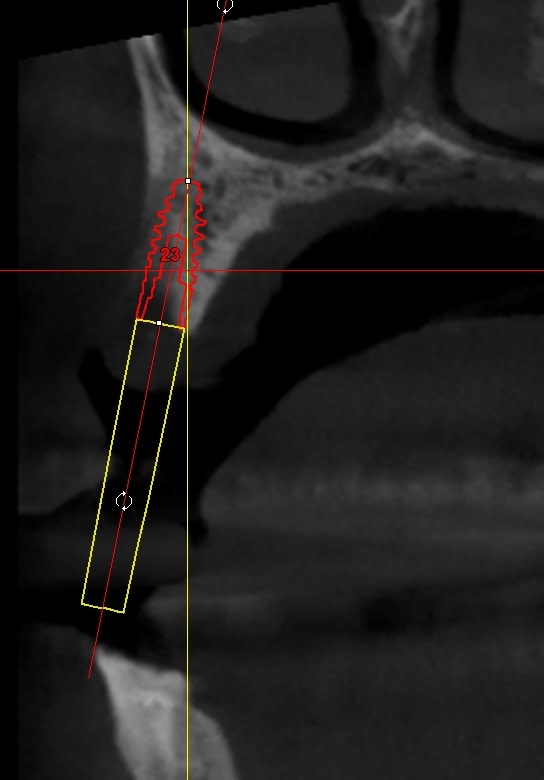

une petite idée du cas, je vais essayer en expansion, puisque c'est mon dada :-)) , et ça permettra de rajouter une vidéo pour pour animer la formation « Expansion Osseuse » à Sallanches les jeudi 4 et vendredi 5 avril 2019 ...

Be ve 23 overview nlkzvu - Eugenol

Be ve 23a 3d muwugo - Eugenol

Be ve123b overview yzsmc3 - Eugenol

Be ver 23 3d sulv8f - Eugenol

Bonjour pour obtenir ton os en vert tu as réalisé une segmentation dans bsp?

c'est pas Blueskyplan....c'est Simplant...